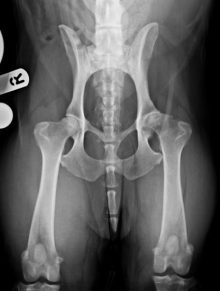

Total Hip Replacement Surgery

Total hip replacement at Eastcott Referrals Swindon During the last 5 years, we have developed a well-established total hip ...

Hip Replacement Surgery

Total Hip Replacement Surgery in Dogs We are now offering total hip replacement using the well-developed and successful Biomedtrix ...